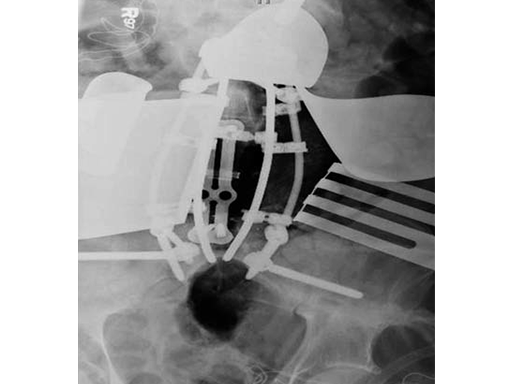

After discussing the risks of surgery, the patient consented to a staged posterior-anterior en bloc spondylectomy. The first stage involved a posterior lumbar pelvic exposure with dissection of the iliopsoas and lumbar plexus. Laminectomy of L3-L5 was performed, with instrumentation from L1 to the ilium bilaterally. Tomita saws were placed at the L3 and L5 disk space.

Stage two was a retroperitoneal exposure of L3-L5 with mobilation of the IVS, aorta, internal common illiac artery and veins, with en bloc resection of the tumor and partial L3 and L5 vertebrectomies.

The vertebral body defect was reconstructed with the PEEK distractible cage, anterior plate, screws, and demineralized bone matrix. Final pathology revealed a true en bloc resection with negative margins.